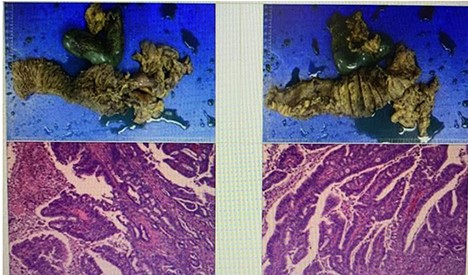

Postoperative pathological report (Fig 5) indicated the following:

Tumor site: pancreatic-head.

Pathological stage: T3N0M0.

Tumor size: 7.3 × 6.8 × 3 cm.

Histological type: ductal adenocarcinoma.

Histological grade: grade IIA.

Surgical margin invasion: there is a cancer involvement found into the duodenal wall, no cancer involvement found in the gastric cutting edge, common bile duct stump.

Lymph node involvement: no lymph node involvement.

Nerve invasion is present. However, no vascular invasion was seen.